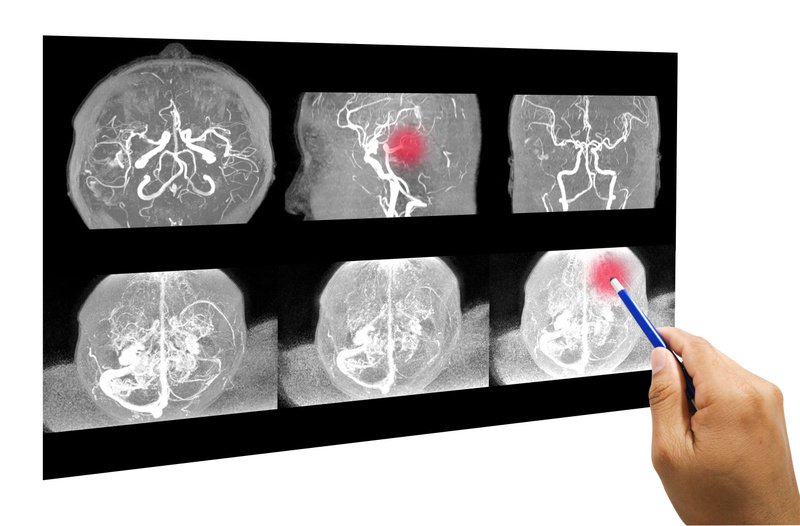

Nyere studier har vist at man basert på seleksjon med avansert avbildningsteknikk kan gi trombolyse til pasienter som tidligere ikke var aktuelle for behandling på grunn av usikkerhet rundt tidspunktet for symptomdebut.